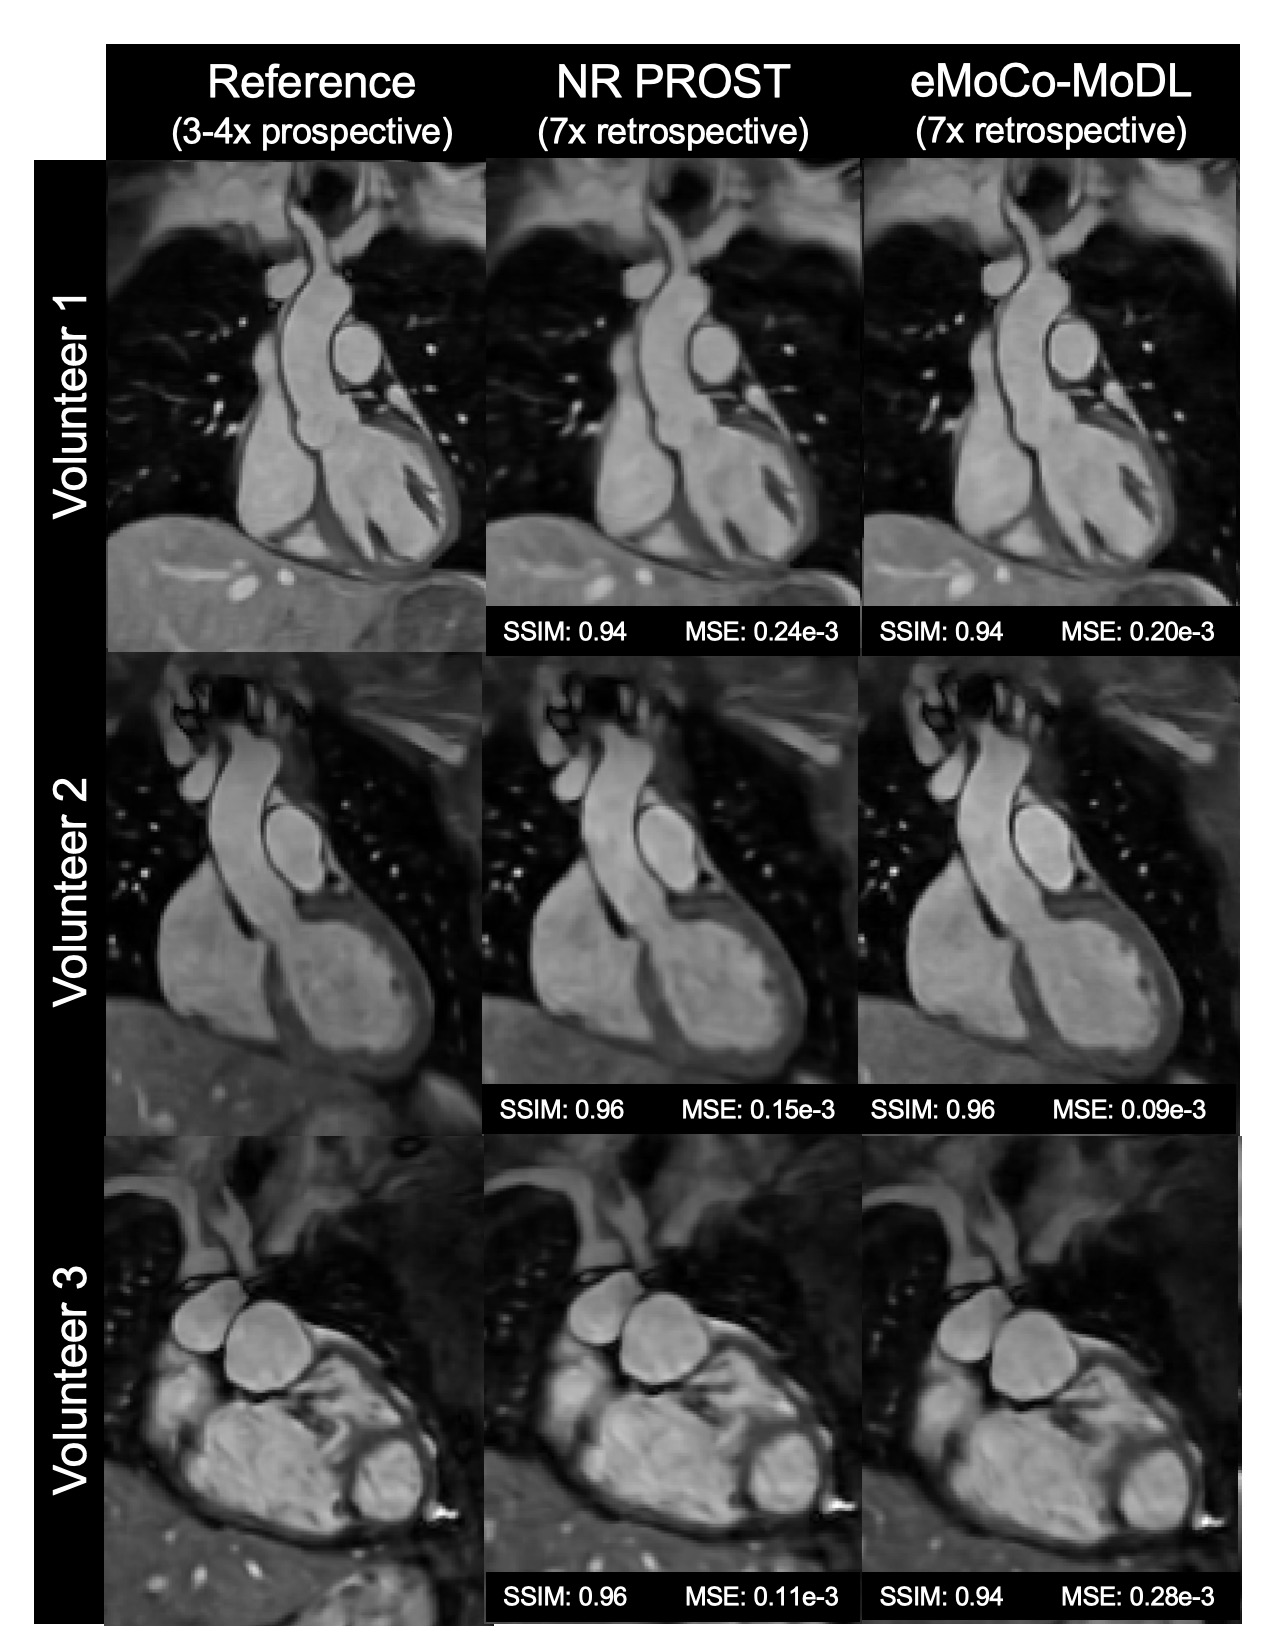

Figure 2: Coronal slices of iNAV-based 3D whole-heart MRI at 0.55T for 3 representative test subjects with 7-fold retrospective undersampling. 2 healthy subjects and 1 CHD patient (third row) are shown. The figure includes reference dataset (4-fold undersampling) reconstructed with NR-PROST (left column), NR-PROST for 7-fold undersampling (middle column), and proposed eMoCo-MoDL for 7-fold undersampling (right column). The SSIM and the MSE was computed for each case.

Figure 3: Coronal slices of iNAV-based 3D whole-heart MRI at 0.55T for 3 representative subjects with 7-fold prospective undersampling. The figure includes reference dataset (4-fold undersampling) reconstructed with NR-PROST acquired in a separate scan (left column), NR-PROST for 7-fold undersampling (middle column), and proposed eMoCo-MoDL for 7-fold undersampling (right column). Sharper details and better visual image quality is observed with eMoCo-MoDL in comparison to NR-PROST.